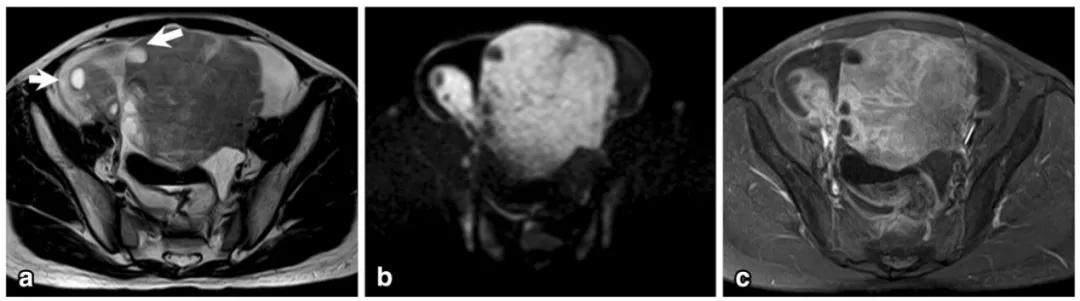

女,65 岁,左侧卵巢纤维瘤。图 a 箭头显示肿物 T2WI 呈低信号,DWI 未见明显扩散受限(b),增强扫描缓慢强化(c 增强早期,d 增强晚期)

女,32 岁,富于细胞性纤维瘤。右卵巢实性为主肿物,T2WI 稍高信号(图 a),DWI 高信号(图 b),增强扫描渐进行强化(c 增强早期,d 增强晚期)